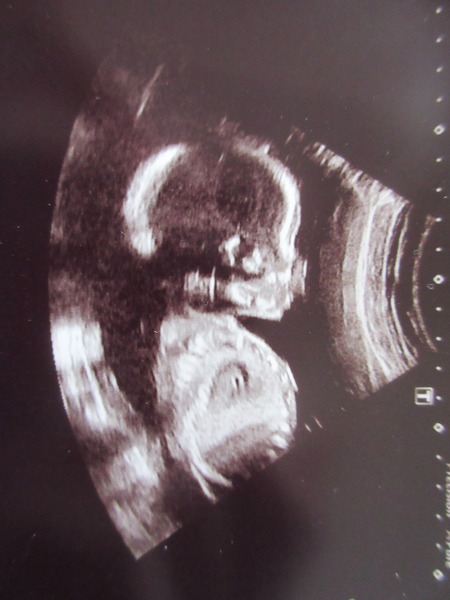

Hi, another good scan here. Baby in an awkward position so I had to go out and drink more water then go back in! Luckily she then managed to see everything. All was well, we are still team yellow, and I don't think the scan gives anything away! But feel free to guess!

Oh, I didn't attach the picture! Try again

OwlinaTree · 01/04/2016 20:13

Owlina I think your baby looks just like mine! I'd hazard a guess we're having the same (boy/girl) or we're long-lost relatives

21+4

Owlina and Zumba My little boy has the same headshape and profile on his ultrasound as yours Wink